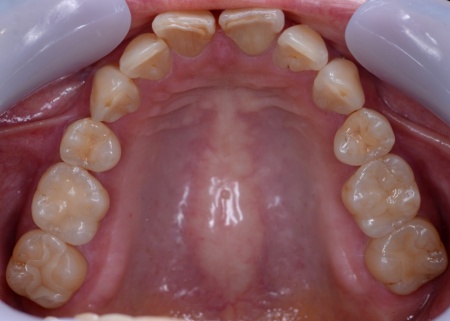

60代女性 すきっ歯が目立つ噛み合わせをワイヤー矯正とアライナー矯正の併用で改善した症例

「以前矯正治療を行ったが、気付いたら前歯がすきっ歯になっていた」とご相談いただきました。

拝見したところ、前歯に隙間が空いており、いわゆるすきっ歯の状態でした。